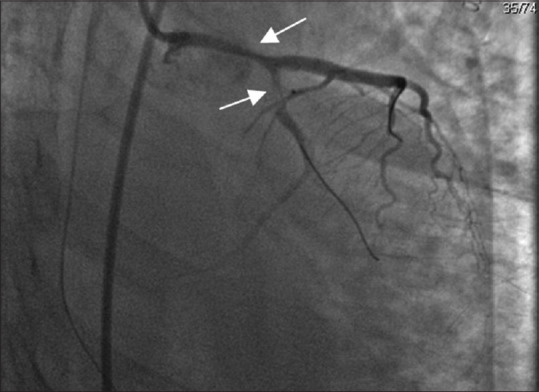

Spontaneous coronary artery dissection is becoming an important cause of acute coronary syndrome, particularly among young women. Its association with female gender, pregnancy, and postpartum period and emotional stress differentiate it from atherosclerotic heart disease. In recent years, there has been more awareness and improved diagnostic and management capabilities, which in turn has increased the diagnostic yield, although knowledge gaps remain. In the present case, a 36-year-old female, who was at 1-month postpartum period, presented with ventricular fibrillation and cardiac arrest. The clinical course was associated with pulmonary hemorrhage. The patient had no current atherosclerotic risk factors, only a family history of sudden cardiac arrest in her mother and sister. She underwent a coronary angiogram, which revealed spontaneous coronary artery dissection (SCAD) in both the left anterior descending and left circumflex artery. Percutaneous coronary intervention was performed but the clinical course was associated with pulmonary hemorrhage. Bronchopulmonary lavage was performed as a diagnostic and therapeutic intervention, and she was discharged in good health. SCAD is an important differential diagnosis in young females presenting with acute coronary syndrome or cardiac arrest. Early recognition and diagnosis are important to decrease the high mortality rate of this disease.